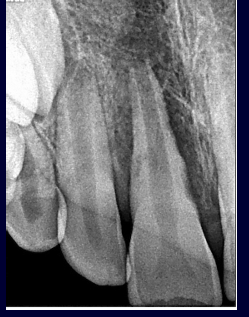

dental trauma- radiographs

-status of root development

-root displacement

-root fracture (take CBCT- likely to see transverse and narrow fractures that may not be caught on 2D radiograph)